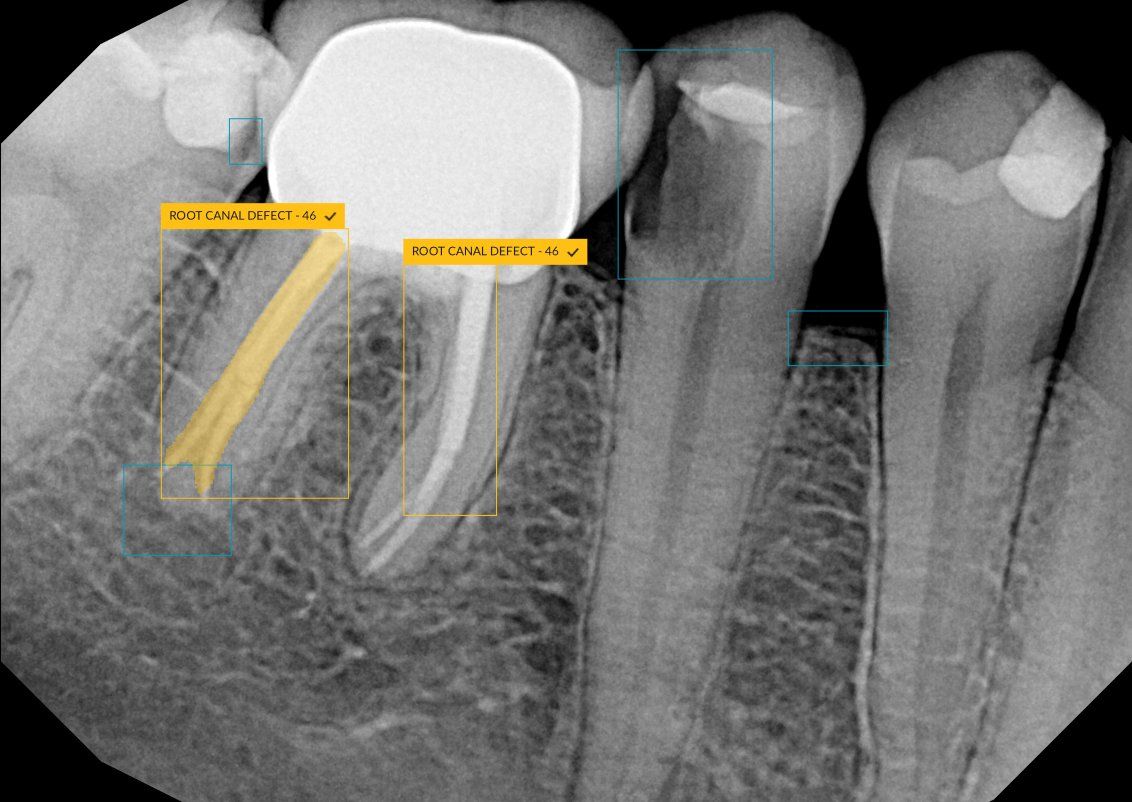

The CS 9600 features breakthrough innovations such as its artificial intelligence (AI)-powered positioning, video cameras, and Live Positioning Assistant to help enable users to produce high-quality images.

“The 5-in-1 CBCT scanner with extraordinary precision.”

"The Swiss Army Knife of diagnostic capabilities.” – Paul Feuerstein, DMD

Technology Insights: CS 9600 from Carestream Dental